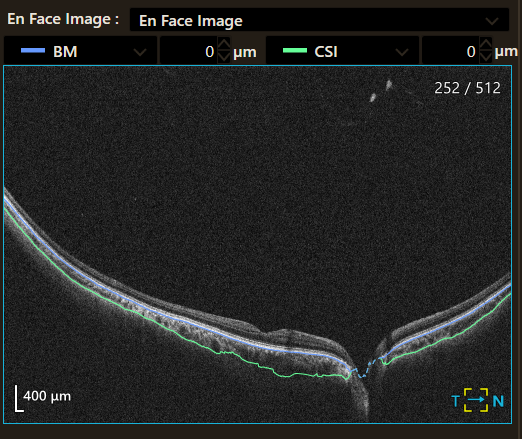

Малюнок 4. Чіткість виявлення межі хоріоідея/склера.